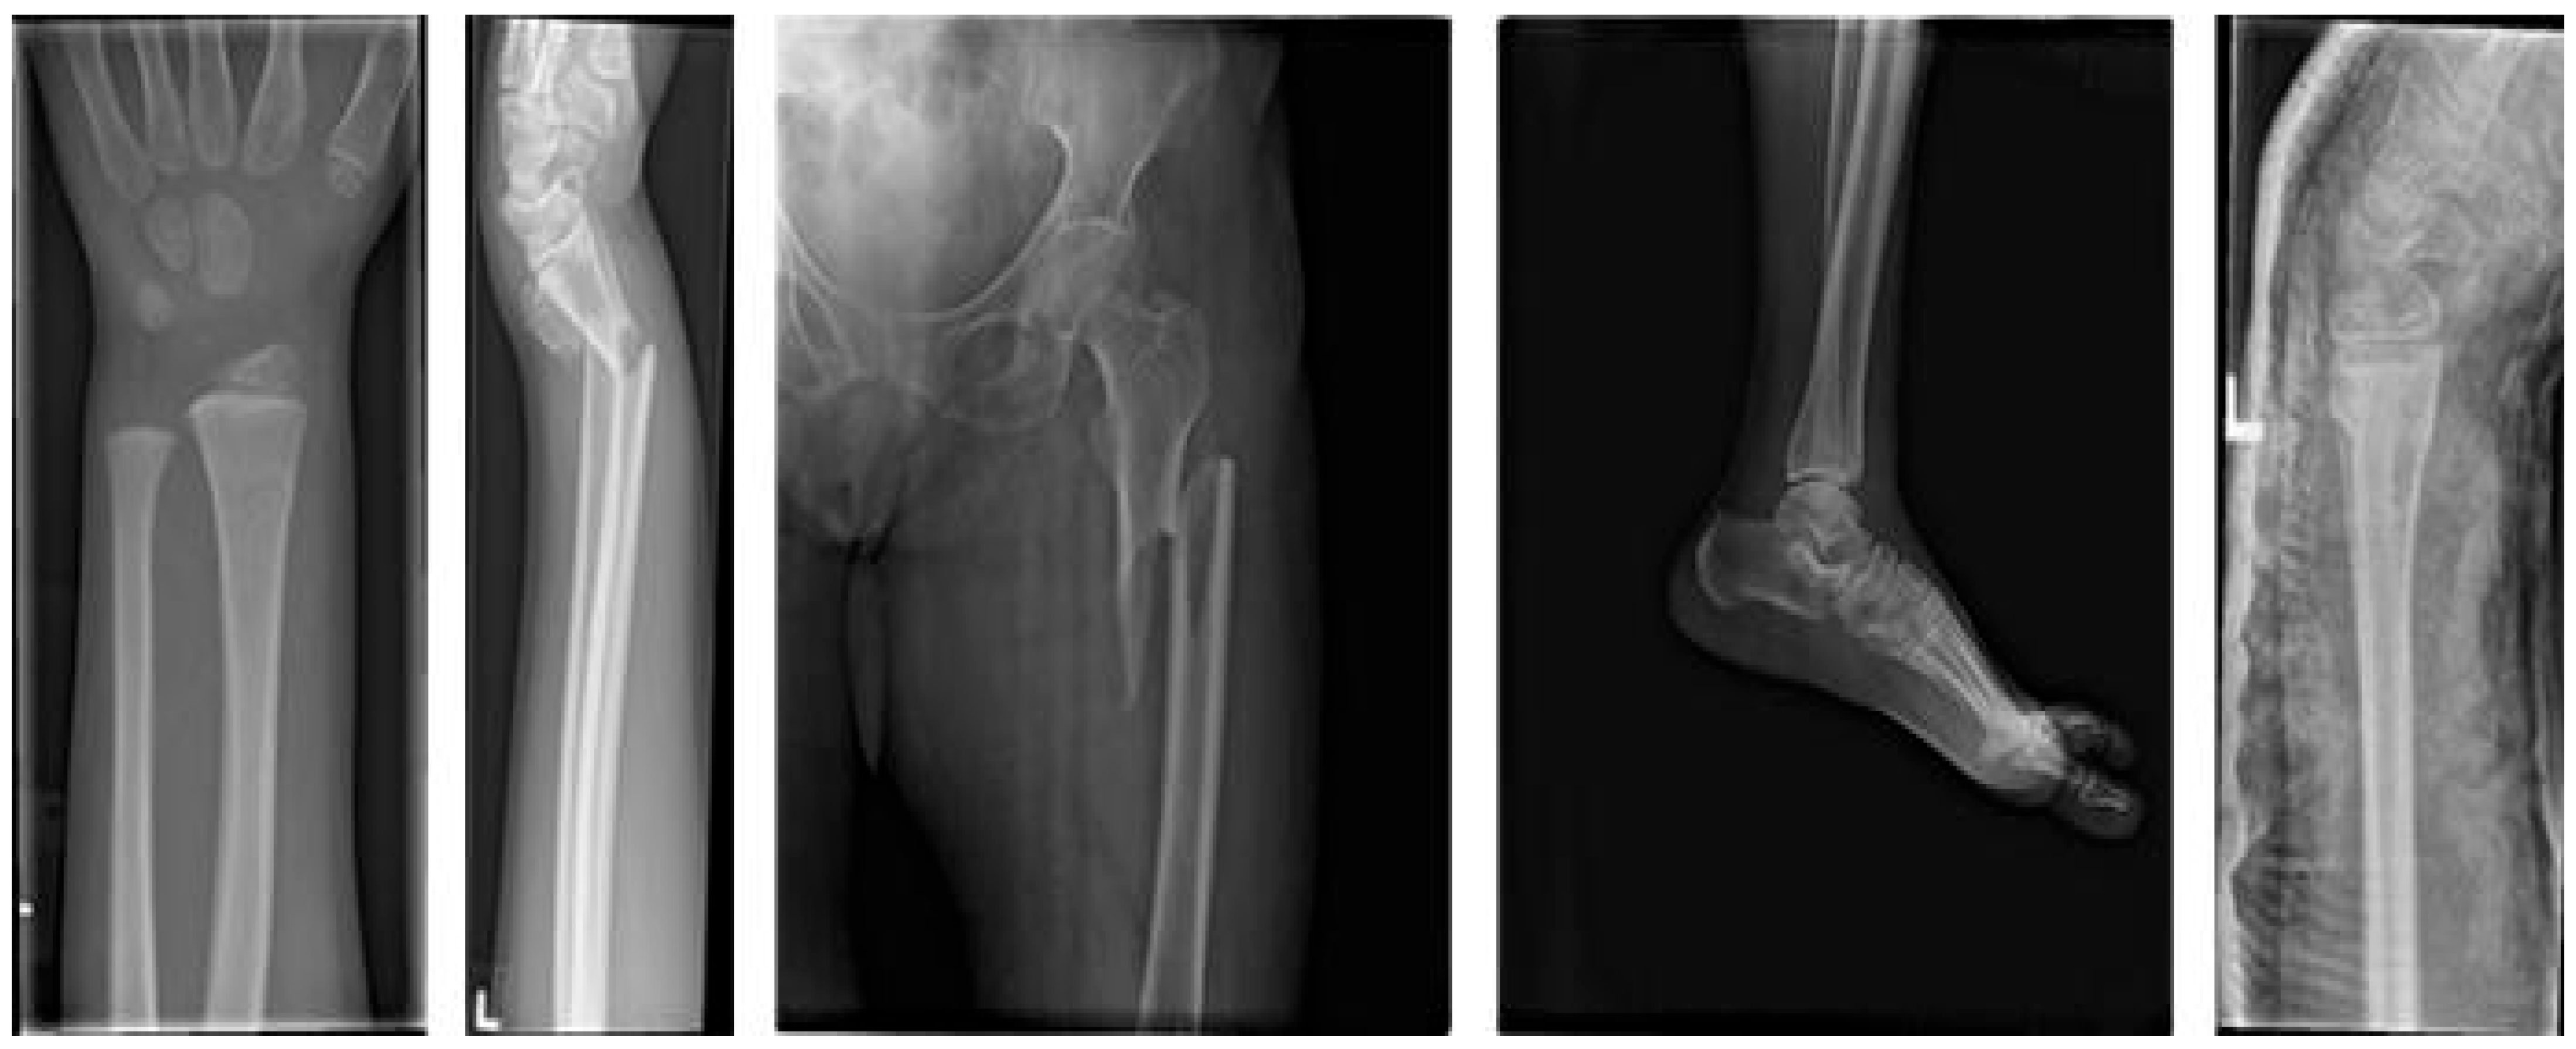

2.1. Acquisition of Medical X-Ray Fracture Images

- Rodrigo, M. Bone Fracture Multi-Region X-Ray Data. Dataset. 2024. Available online: https://www.kaggle.com/datasets/bmadushanirodrigo/fracture-multi-region-x-ray-data/data (accessed on 5 May 2025).